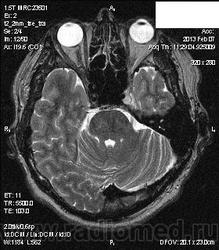

Здравствуйте! Уже писала сегодня сообщение по поводу последнего опубликованного Вами случая, но по каким-то причинам оно не отображается. Не складывается ли у Вас впечатление о наличии интрамуральной гематомы в кавернозном сегменте левой ВСА, с расширением наружного диаметра артерии и эксцентричным расположением просвета сосуда (диссекция). Не проводилась ли пациенту исследование интракраниальных артерий; с какими жалобами обратился пациент?

В анамнезе частые головные боли около года. Складывается впечатление, что зона патологических изменений прилежит к латеральной стенке кавернозного синуса, нерезко оттесняет прилежащие отделы левой ВСА. По поводу диссекции думала, но не видела в этом отделе, поэтому сомневаюсь. Исследование интракраниальных сосудов не проводилось.

Большое спасибо, Валентин Львович. Не знаю, стоит ли высказываться в пользу диссекции ВСА или больше данных за объемное образование?

Я бы в первую очередь подумала о диссекции.

А такое накопление контраста характерно для диссекции?

Здесь должна быть разная скрость накопления КВ, менингиома накапливает медленнее ( да и как-то не похоже на нее), можно сделать РКТ для установления гиперостоза матрикса( для исключения менингиомы) . При назначении аникоагулянтов должен быть эффект.

При контрастном усилении наблюдаются истинный и ложный поток. разделенные линейной полоской

Если все-таки думать о диссекции и об интрамуральной гематоме, то какой стадии трансформации крови это сответствует? Сигнальные характеристики не подходят ни острой, ни подострой, ни хронической стадии кровоизлияния.

Через 4 дня на томограммах по Т1 ВИ сохраняется изоинтенсивный МР-сигнал от загадочной зоны в области левого кавернозного синуса. Рекомендовала МСКТ-ангиографию. Если через неделю будет известен результат, то сообщу.

Если это диссекция ВСА, то почему она копит контраст? А вот кавернозный синус в принципе должен копить...